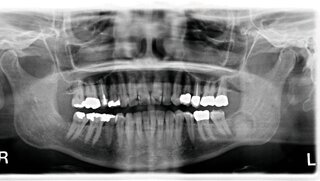

IndienOdontom: Ärzte ziehen Teenager 82 Zähne! Fünf Jahre litt ein 17-jähriger Teenager aus Indien an einem komplexen Odontom. Jetzt wurde er in einer Spezialklinik behandelt: In der dreistündigen Operation wurden 82 Zähne aus seinem Kiefer entfernt. 15.07.2021 ZahnmedizinChirurgie